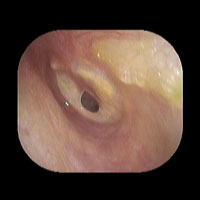

右急性中耳炎(中等症)

鼓膜がやや赤くなっています。鼓膜の奥に膿が透けて見えています。鼓膜の腫れはありません。抗生剤の内服で鼓膜切開を行わずに16日目で治りました。

初診日

7日目

14日目

16日目